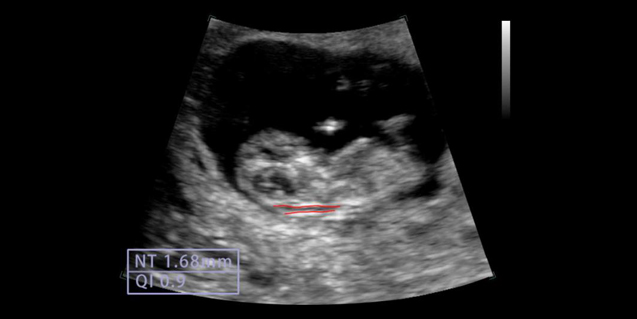

腹部,胎儿检查